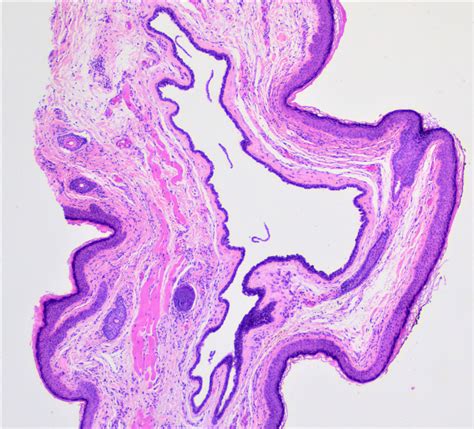

• Sebaceous Cyst: A slow-growing, benign sac beneath the skin that contains fluid or cheesy material. These can happen anywhere on the skin, including the eyelids.